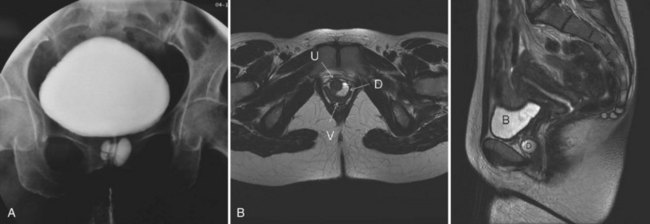

Acquired (also termed “secondary”) diverticula occur most commonly in the setting of bladder outlet obstruction or neurogenic vesicourethral dysfunction. Similar to the congenital type, these diverticula are also located most commonly at the ureterovesical hiatus (Van Arsdalen and Wein, 1992) but also occur elsewhere in the bladder. Acquired diverticula in males usually occur after age 60, which corresponds to the age of the development of prostatic enlargement (Fig. 78–2). Bladder outlet obstructions, including those due to benign and malignant disease of the prostate or urethral stricture, are commonly associated factors in adults, although obstruction is not considered to be present in all cases (Blacklock et al, 1983). Acquired diverticula are often multiple, typically found in association with significant bladder trabeculation (Wesselhoeft et al, 1963), and much more common in males than females (Senger et al, 1952; Pool and Hacker, 1966). Bladder diverticula in females are uncommon (Gillon et al, 1988) and quite rare in the absence of obstruction (Safir et al, 1998) (Fig. 78–3). Historically, the reported prevalence of moderate- to large-sized bladder diverticula in association with “prostatism” is approximately 1% to 6% (Burns, 1944). It is important to note that an acquired bladder diverticulum may also be found in children and young adults secondary to a number of conditions, including bladder neck dysfunction, posterior urethral valves, and neurogenic vesicourethral dysfunction. If the diverticulum encompasses the ureteral orifice in the setting of a neurogenic bladder and vesicoureteral reflux, it is termed a “Hutch” diverticulum (Hutch, 1952). These diverticula may also occur in the setting of dysfunctional voiding.

Figure 78–2 Voiding cystourethrogram (VCUG) demonstrating a bladder diverticulum in a male. A, The diverticulum is seen posterior to the bladder on this lateral voiding image (arrow points to urethra). There is a fluid-fluid level within the diverticulum representing the relatively denser contrast media settling below the urine. B, Later image from the VCUG demonstrates near emptying of the bladder with enlargement of the diverticulum.

Figure 78–3 Bladder and urethral diverticula in a female. A, MRI of a bladder diverticulum. B, Endoluminal MRI demonstrating urethral diverticulum (arrow points to urethral diverticulum). B, bladder; D, bladder diverticulum.